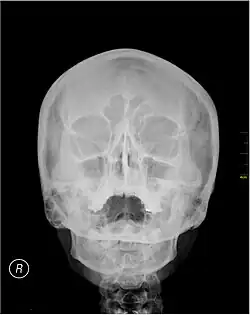

Waters' view

A Waters' view radiograph showing the paranasal sinuses

Waters' view (also known as the occipitomental view or parietoacanthial projection) is a radiographic view of the skull. It is commonly used to get a better view of the maxillary sinuses. An x-ray beam is angled at 45° to the orbitomeatal line. The rays pass from behind the head and are perpendicular to the radiographic plate. Another variation of the waters places the orbitomeatal line at a 37° angle to the image receptor. It is named after the American radiologist Charles Alexander Waters.